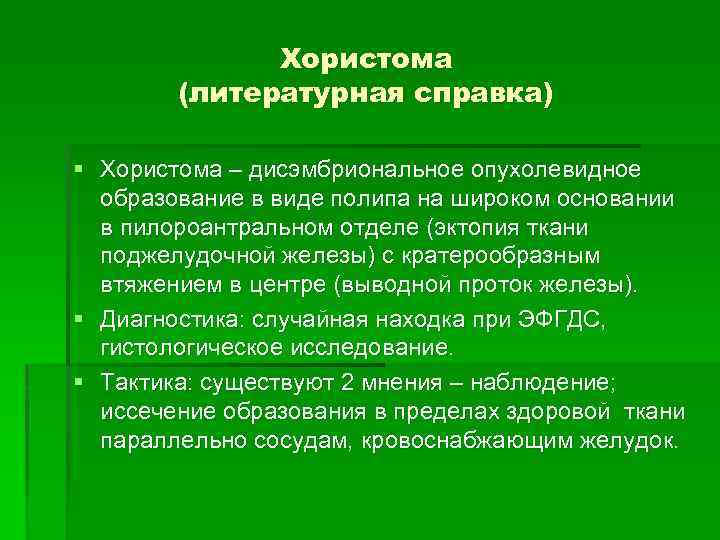

Хористома (литературная справка) § Хористома – дисэмбриональное опухолевидное образование в виде полипа на широком основании в пилороантральном отделе (эктопия ткани поджелудочной железы) с кратерообразным втяжением в центре (выводной проток железы). § Диагностика: случайная находка при ЭФГДС, гистологическое исследование. § Тактика: существуют 2 мнения – наблюдение; иссечение образования в пределах здоровой ткани параллельно сосудам, кровоснабжающим желудок.